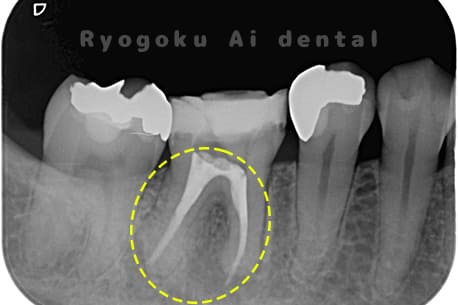

Case29

-

- 原因

- 慢性根尖性歯周炎

- 治療内容

- マイクロエンド治療

- 治療費用

- 121,000円(別途被せ物費用発生)

- 担当医

- Dr. 炭野

右下が噛むと痛いとのことでご来院された患者様です。マイクロエンド治療を行いました。

<リスク・副作用>

術後は痛み、腫れ、痺れなどの副作用が生じる場合があります。症状が再発する可能性があります。